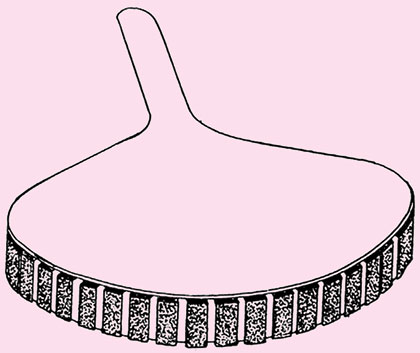

Curved or Convex Array Transducer

Curved scanners are predominatly used in abdominal sonography with frequencies from 2.5 MHz (obese patients) to 5 MHz (thin patients) with the mean value around 3.5–3.75 MHz (Fig. 1.17).

This produces a scan somewhere between those of linear and sector scanners and is therefore used for all parts of body except for specialized echo cardiography.